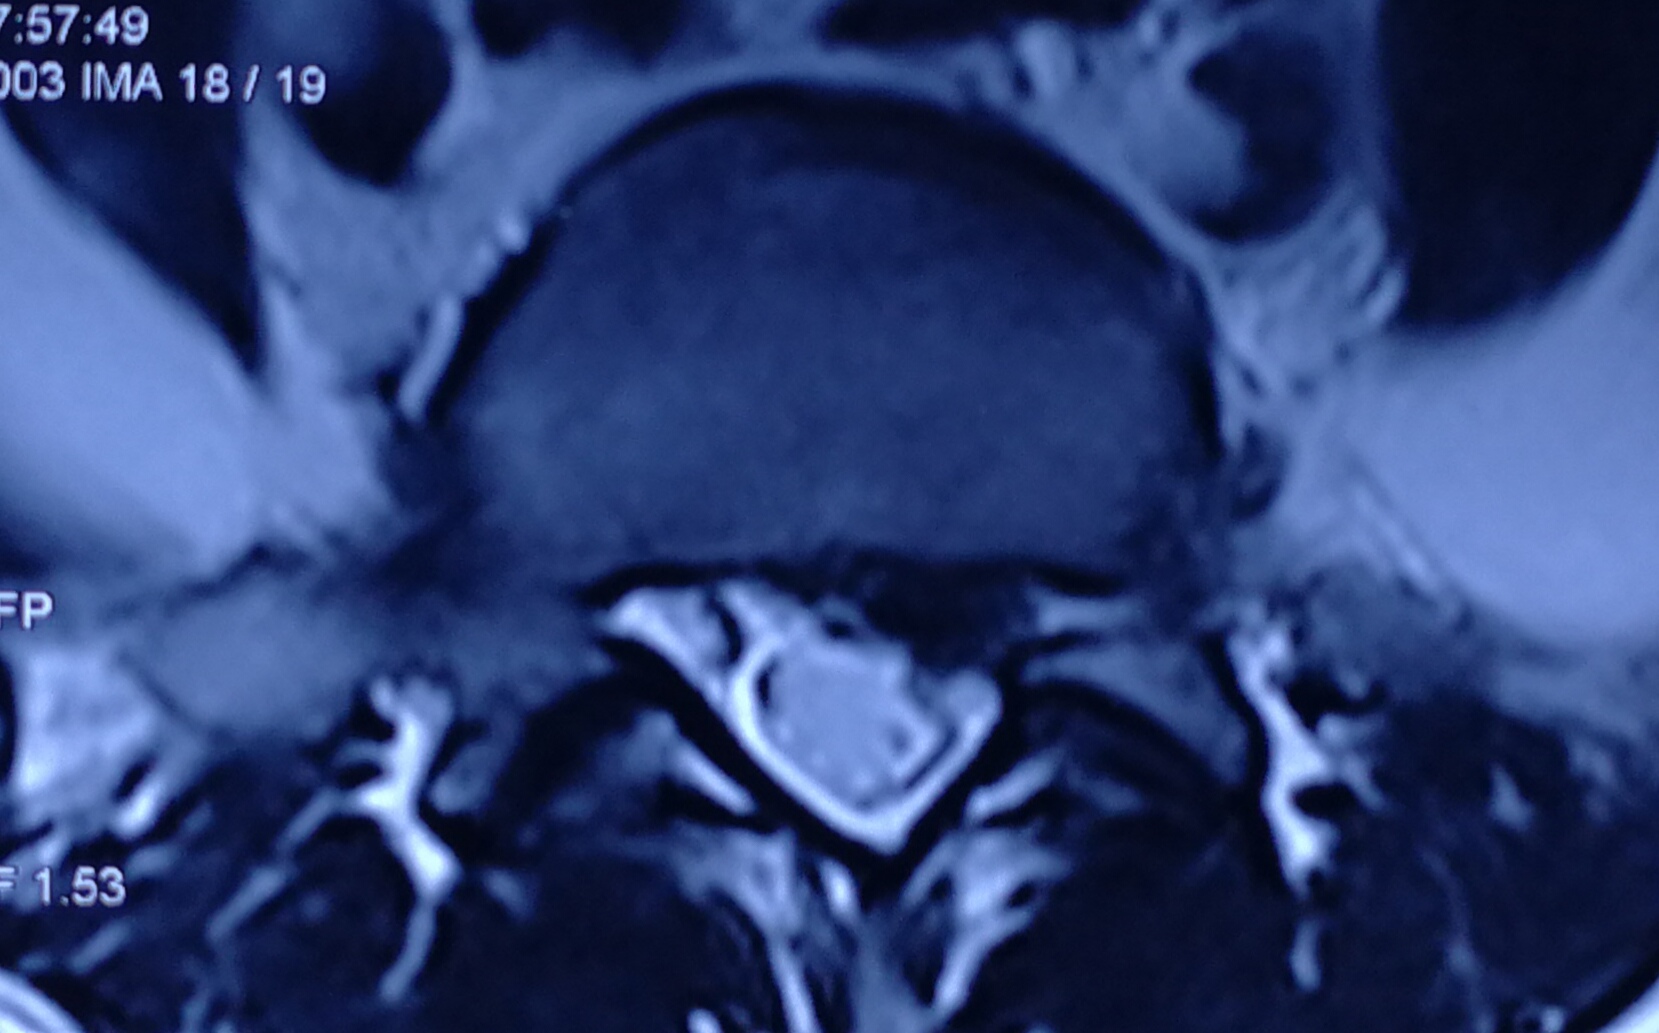

从磁共振片子上看,突出间隙位于腰4、5和腰5骶1,以腰5骶1间隙的椎间盘突出尤为明显,属于左后方的巨大突出,腰5神经根明显被挤压,已经看不清神经的走向,但右侧的神经根影子十分清楚,出现患肢的麻木也就是理所当然的了。目前体检发现左下肢直腿抬高试验40度阳性,加强试验阳性,右侧均为阴性,左侧小腿后外侧及足背外侧也有片状皮肤感觉减退区域,左侧跟腱反射微微有些减弱,右侧是正常的,看得出,骶1神经根是受到了一定的伤害。